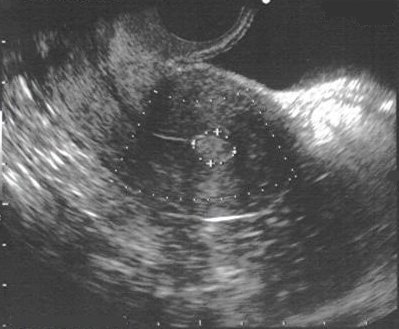

Os pólipos aparecem na USG sob a forma de um espessamento endometrial inespecífico ou

como estruturas glandulares e císticas flutuantes (Muylder, 1999).

USG de pólipo endometrial - paciente submetida a ressecção histeroscópica pelo Prof. Doutor João Bernardes.